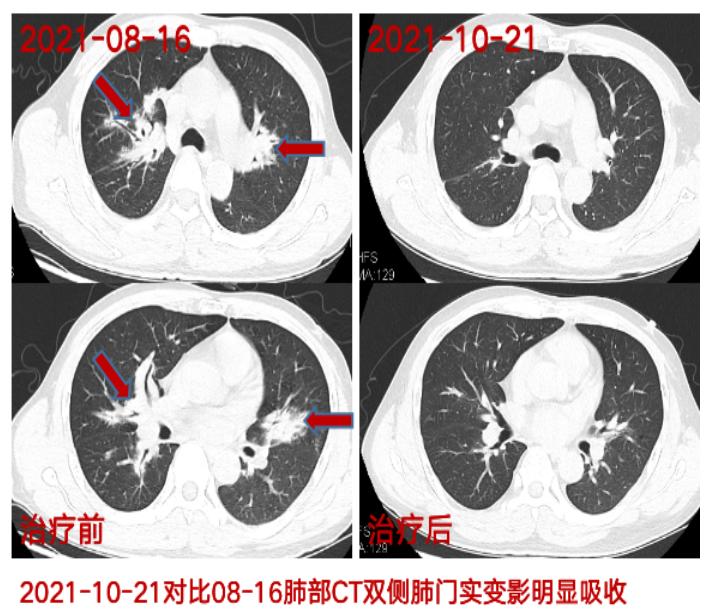

接诊的徐主任凭借多年经验,发现胡大叔的反应能力比同龄人似乎慢一些,眼睛里还布满了血丝,徐主任感觉这个情况不简单,建议胡大叔立即先做一个肺部CT检查。通过肺部CT可以看到,沿着胡大叔两边的肺门分布着一些实变影,经验丰富的徐主任马上意识到胡大叔的病情可能比预想的要复杂,于是让胡大叔住院做进一步检查。住院期间发现胡大叔还同时患有鼻窦炎、结膜炎、听力下降、血尿、下肢血栓,并对其肺部进行了气管镜检查。

目前,在徐主任团队及时精准化、规范化的专业治疗下,胡大叔的症状得到了明显改善,情况也越来越好。前些时间,胡大叔来院复诊,复查肺部CT显示两边肺门实变影较前明显吸收,重新享受畅快幸福的呼吸。

附患者部分检查结果及治疗前后对比图片: